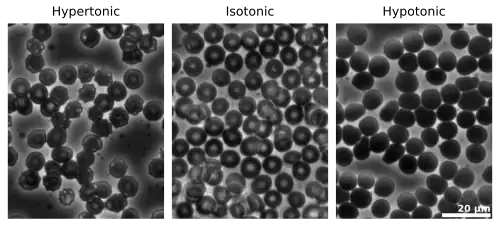

A typical human red blood cell has a disk diameter of approximately 6.2–8.2 μm[19] and a maximum thickness of 2–2.5 μm and a minimum thickness in the centre of 0.8–1 μm, being much smaller than most other human cells. These cells have an average volume of about 90 fL[20] with a surface area of about 136 μm2, and can swell up to a sphere shape containing 150 fL, without membrane distension.

Senescence

The aging red blood cell undergoes changes in its plasma membrane, making it susceptible to selective recognition by macrophages and subsequent phagocytosis in the mononuclear phagocyte system (spleen, liver and lymph nodes), thus removing old and defective cells and continually purging the blood. This process is termed eryptosis, red blood cell programmed death.[64] This process normally occurs at the same rate of production by erythropoiesis, balancing the total circulating red blood cell count. Eryptosis is increased in a wide variety of diseases including sepsis, haemolytic uremic syndrome, malaria, sickle cell anemia, beta-thalassemia, glucose-6-phosphate dehydrogenase deficiency, phosphate depletion, iron deficiency and Wilson's disease. Eryptosis can be elicited by osmotic shock, oxidative stress, and energy depletion, as well as by a wide variety of endogenous mediators and xenobiotics. Excessive eryptosis is observed in red blood cells lacking the cGMP-dependent protein kinase type I or the AMP-activated protein kinase AMPK. Inhibitors of eryptosis include erythropoietin, nitric oxide, catecholamines and high concentrations of urea.